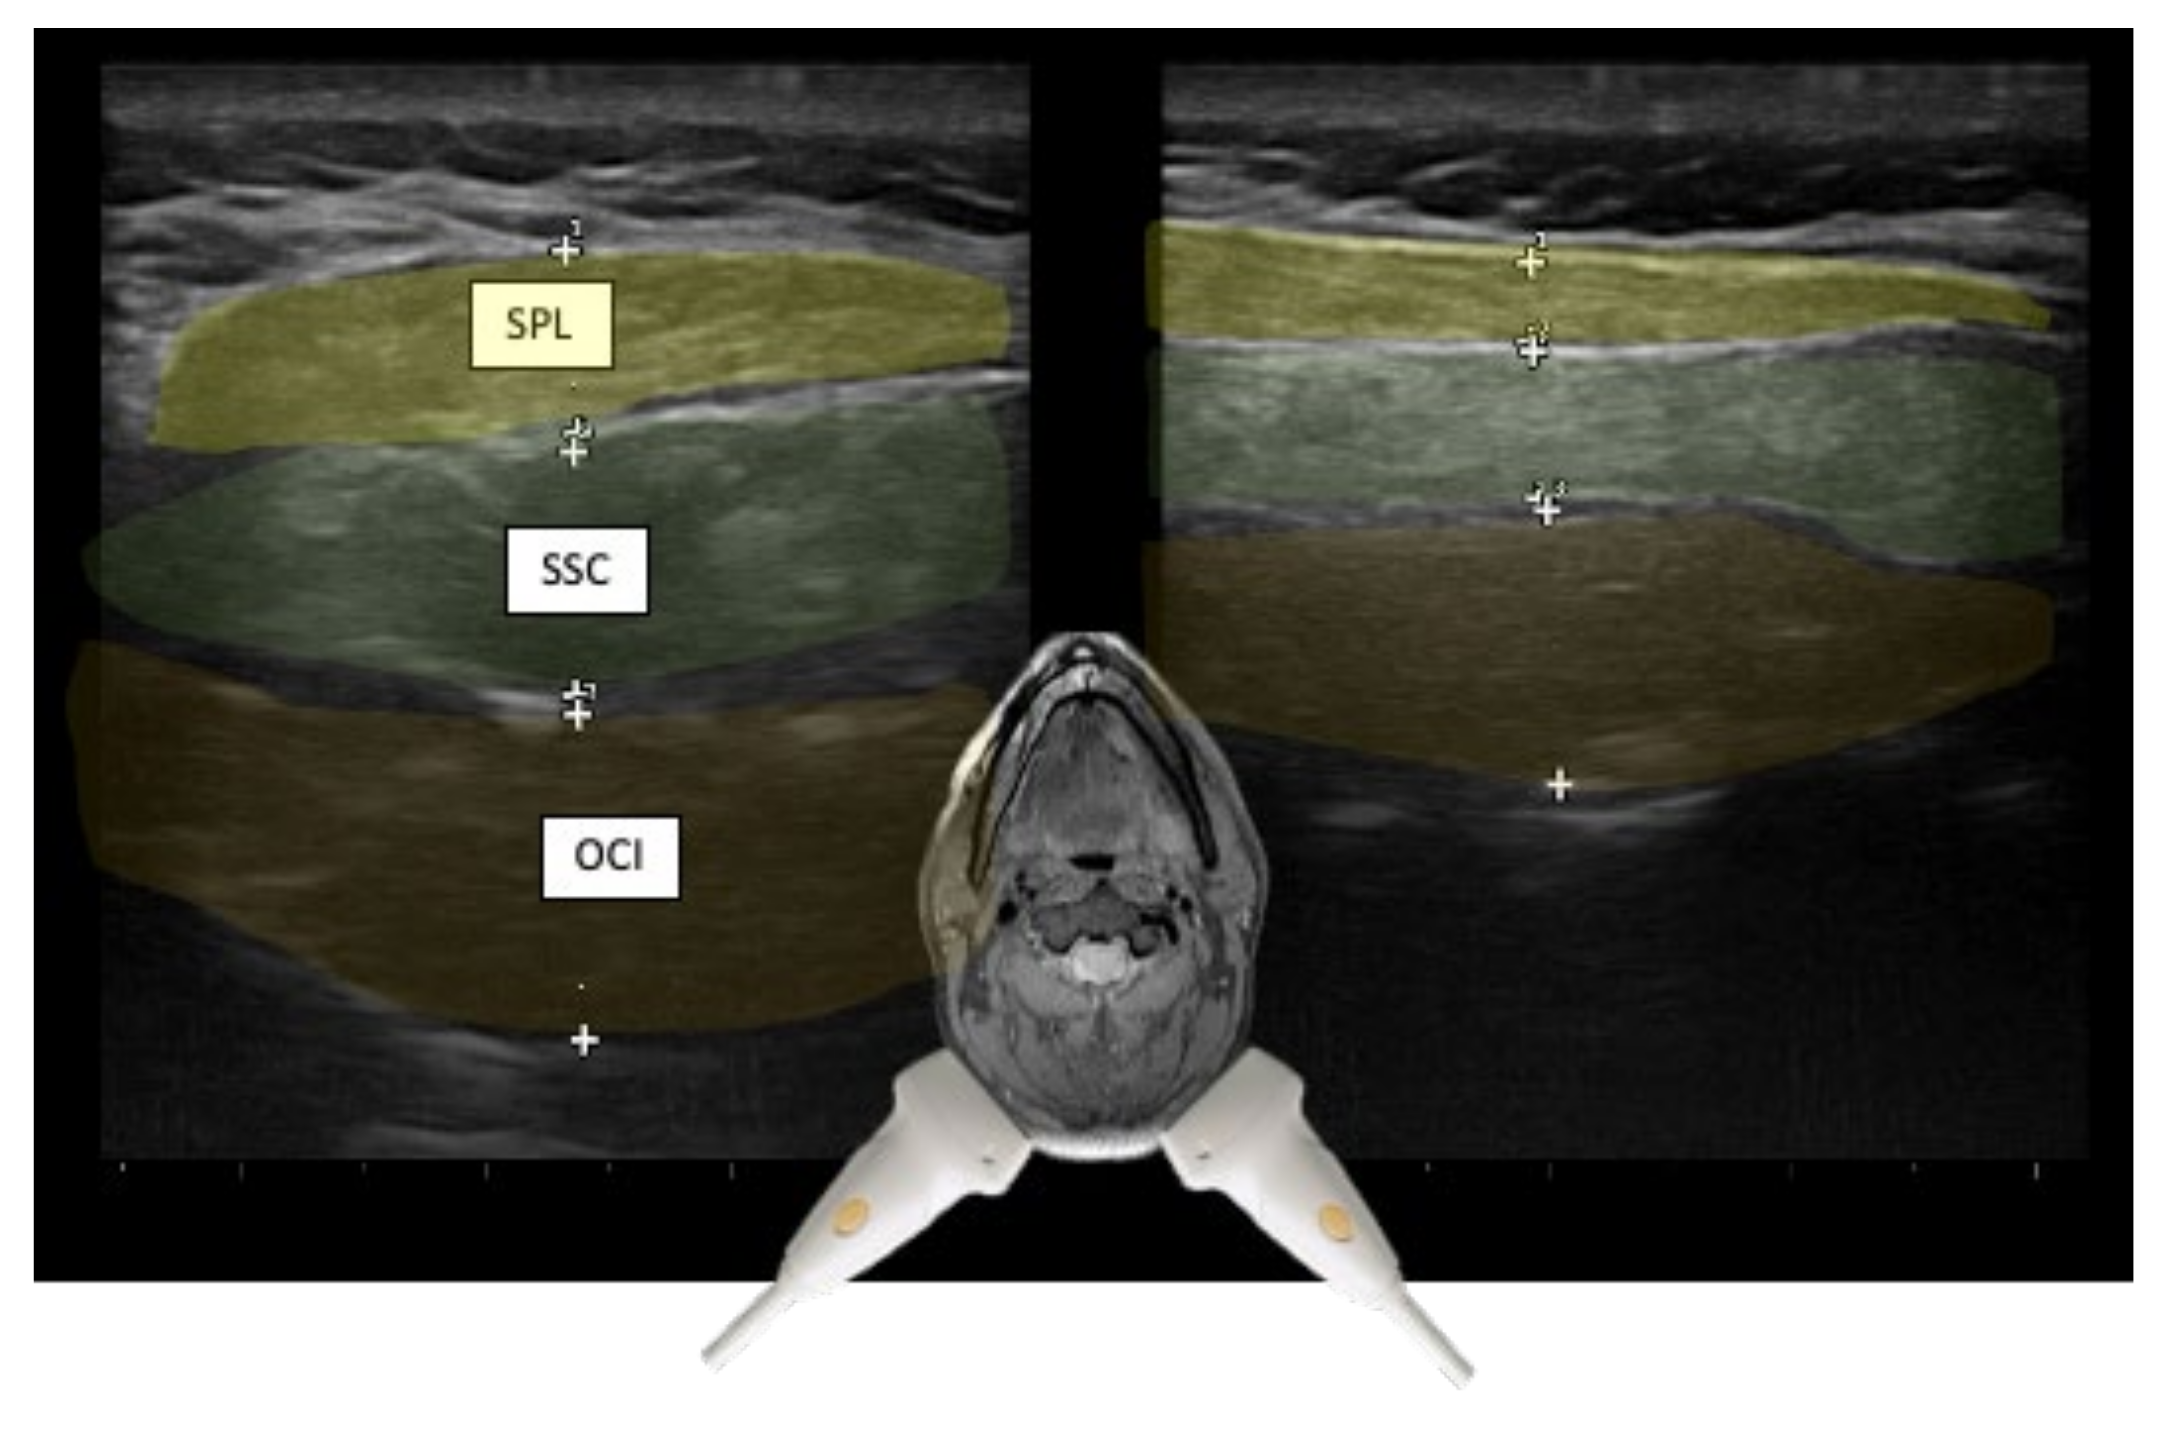

3.1. Layers and Compartments

3.2. Orientation of Layers—Reciprocal Function of Neighboring Structures

| Semispinalis capitis (SSPcap) | Extension of head | + | + | SPLcap, OCI | Strongest extensor muscle of head and neck |

| Semispinalis cervicis (SSPcer) | Extension of neck | + | + | SPLcer, TRA | |

| Splenius capitis (SPLcap) | Ipsiversion of head | ++ | ++ | major occipital nerve, SPLcap/cer, LSMcap, OCI | Prominent reduction in bulk from repeated injections possible |

| Splenius cervicis (SPLcer) | Ipsiversion of neck | +++ | ++ | LEV, TRA, Longissimus cervicis | Relevant for full turn of the neck |

| Longissimus capitis (LCM) | Ipsiversion of head and neck | +++ | ++ | SPLcap, SSPcap | Obligatory USG |

| Obliquus capitis inferior (OCI) | Ipsiversion of head | +++ | +++ | SSPcap, RCM, vertebral artery, greater occipital nerve | Adjacent muscles are all extensors of the head |